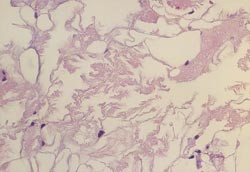

MR cerebrum viste utvidede ventrikler, grovt overflaterelieff og noe økt signalintensitet periventrikulært (fig 2). Skjelettrøntgen av hender og føtter viste cystiske oppklaringer i en rekke knokler (fig 3). Det var også mulig cystedanning i trochanterregionen og en usikker cystedanning i buen av C1. Det ble for øvrig ikke funnet cyster i aksialskjelett, dvs. cranium, columna, thorax og bekken. Ved histologisk undersøkelse av cystemateriale fra finger fant man et bilde som svarer godt til det som beskrives ved PLO-SL (fig 4). EEG viste abnorm aktivitet frontotemporalt bilateralt. Det var ingen epileptiform aktivitet. ”Brain stem auditory evoked response” (BAER) var unormal på venstre side, med ikke-reproduserbare potensialer ved repetert undersøkelse. Normal ”visual evoked response” (VER) og ”somatosensory evoked response” (SER). I spinalvæsken fant man forhøyet totalprotein, 0,73 g/l. Ved nevropsykologisk testing var det tydelig subnormal generell funksjon, med nedsatt sensorimotorisk funksjon, redusert psykomotorisk tempo, uttalt svekkelse i hukommelsen, særlig for verbalt materiale, og perseverasjonstendens. Resultatene antydet at svekkelsen var relativt størst for funksjoner knyttet til venstre hemisfære. Man konkluderte med at utfallene var forenlige med betydelig grad av demens.

Beincystene er fylt med delvis nekrotisk fettvev og inneholder to komponenter:

• – Cysterom fylt med triglyserider

• – Eiendommelige 1 – 2 µ m tykke, foldede og ultrastrukturelt karakteristiske, autofluorescerende membraner i dobbelt lag

Membranene og de laminære strukturer består av karbohydrater, lipider og fosfolipider (10) som omgir fettsyrekrystaller, hydroksyapatittkrystaller og kollagenholdig bindevev.